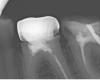

Kambriel Опубликовано 27 ноября, 2009 Автор Поделиться Опубликовано 27 ноября, 2009 Ну вот, дерни за веревочку- она и потянется... Была в другой клинике, консультировалась с ортопедом. Под металлическими коронками, говорит, мы можем увидеть только кариес, так что о состоянии стенок судить невозможно. Корни, сказал, нормальные. Но, как оказалось, 6-й зуб слева под коронкой почерневший (прикладываю фото, там видна темная полоса под коронкой- это зуб), а значит, мол, его опасно расцементировать. Сказал: "Вплоть до удаления. Так что вы должны быть готовы к тому, что если он развалится, то поставить имплантат." Но ведь меня не беспокоят зубы под коронками и то, что коронки короткие тоже. Жевала же 22 года. Я их регулярно чищу. Меня- то волнует 7-й слева. А мне врач сказал, что 7-й нужно накрывать вместе с 6-м, чтобы они друг друга держали. Вопрос: разве не лучше поставить коронку только на 7-й зуб? Ведь если что случится с одним зубом, тогда надо будет снимать коронку и с другого. И не трогать вообще пока эти шестерки, что под коронками? Уважаемые врачи, что посоветуете? Вот фото: И еще визиограмма 6-й и 7-й, что со штифтом. Вот еще и корни отдельно. Ссылка на комментарий

Kambriel Опубликовано 27 ноября, 2009 Автор Поделиться Опубликовано 27 ноября, 2009 (изменено) оба зуба на рентгене можно и нужно спасать. перепломбировывать качественно каналы, делать культевую вкладку разборную в оба зуба и одиночные коронки (не нужно их соединять, они сами по себе будут отлично держаться - но удлинить коронковую часть зуба - необходимо) - по вкусу: от литой до м/керамической на цирконии. Неужели все так плохо?! Так вот же врач и предупредил меня, что перепломбировать каналы в почерневшем зубе (он как- то назвал это терминологически), может оказаться невозможным и сказал, что в принципе, можно пока и не снимать коронку. Что ж тогда ходить, пока корни не развалятся? А культевые вкладки из чего лучше сделать в моем случае. И что такое металлокерамическая на цирконии? Я думала, что существует металлокерамическая и безметалловая из ДЦ. P.S. Только я заикнулась про диоксид циркония, как вызвала сильное раздражение у доктора. Мол, сидит, умничает. И мне было сказано, что это я только слышала, что они самые крепкие, на самом деле это далекооо не так. Теперь боюсь даже заикнуться про культевую вкладку. Да еще разборную. Изменено 27 ноября, 2009 пользователем Kambriel Ссылка на комментарий